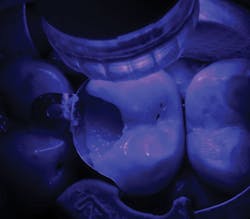

The tooth was anesthetized using 4% articaine with 1:200,000 epinephrine x 1.8 cc. The upper left posterior quadrant was isolated using a rubber dam. Following removal of the restoration (figure 4), gross caries was removed using a #6 round stainless steel slow-speed carbide followed by #6 and #4 round slow-speed polymer SmartBurs II (SS White). Complete caries removal was determined by explorer examination and evaluating the existence of cariogenic bacteria using fluorescence (Spectra, Air Techniques). A Triodent sectional matrix system (Ultradent) was placed (figure 5), followed by the application of a base layer using Ionolux RMGI (figure 6). In addition, the Ionolux RMGI was selected for this case due to its high compressive strength, approaching levels seen with the newest generation of flowable composite resins. (8,9) The Ionolux was compressed into the preparation in what was the initial layer of the open sandwich technique. Following the light-curing of the Ionolux (figures 7 and 8), Futurabond U (Voco), a dual-cure universal adhesive in a single-dose delivery system, was applied to the preparation and light-cured (figure 9). Admira Fusion (Voco), a universal light-cured, nanohybrid, organically modified ceramic (ORMOCER), was placed in 2-mm increments. Each increment was light-cured until the restoration was completed (figures 10 and 11). A radiograph was taken to evaluate the immediate success of the restoration (figure 12). The Ionolux RMGI demonstrated excellent opacity, comparable to composite resins.